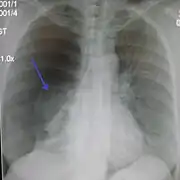

Lateral inspired X-ray at the same time, more clearly showing the pneumothorax posteriorly in this case

It is not unusual for the mediastinum (the structure between the lungs that contains the heart, great blood vessels, and large airways) to be shifted away from the affected lung due to the pressure differences. This is not equivalent to a tension pneumothorax, which is determined mainly by the constellation of symptoms, hypoxia, and shock.[13]

The size of the pneumothorax (i.e. the volume of air in the pleural space) can be determined with a reasonable degree of accuracy by measuring the distance between the chest wall and the lung. This is relevant to treatment, as smaller pneumothoraces may be managed differently. An air rim of 2 cm means that the pneumothorax occupies about 50% of the hemithorax.[15] British professional guidelines have traditionally stated that the measurement should be performed at the level of the hilum (where blood vessels and airways enter the lung) with 2 cm as the cutoff,[15] while American guidelines state that the measurement should be done at the apex (top) of the lung with 3 cm differentiating between a "small" and a "large" pneumothorax.[33] The latter method may overestimate the size of a pneumothorax if it is located mainly at the apex, which is a common occurrence.[15] The various methods correlate poorly but are the best easily available ways of estimating pneumothorax size.[15][19] CT scanning (see below) can provide a more accurate determination of the size of the pneumothorax, but its routine use in this setting is not recommended.[33]

Not all pneumothoraces are uniform; some only form a pocket of air in a particular place in the chest.[15] Small amounts of fluid may be noted on the chest X-ray (hydropneumothorax); this may be blood (hemopneumothorax).[13] In some cases, the only significant abnormality may be the "deep sulcus sign", in which the normally small space between the chest wall and the diaphragm appears enlarged due to the abnormal presence of fluid.[16]